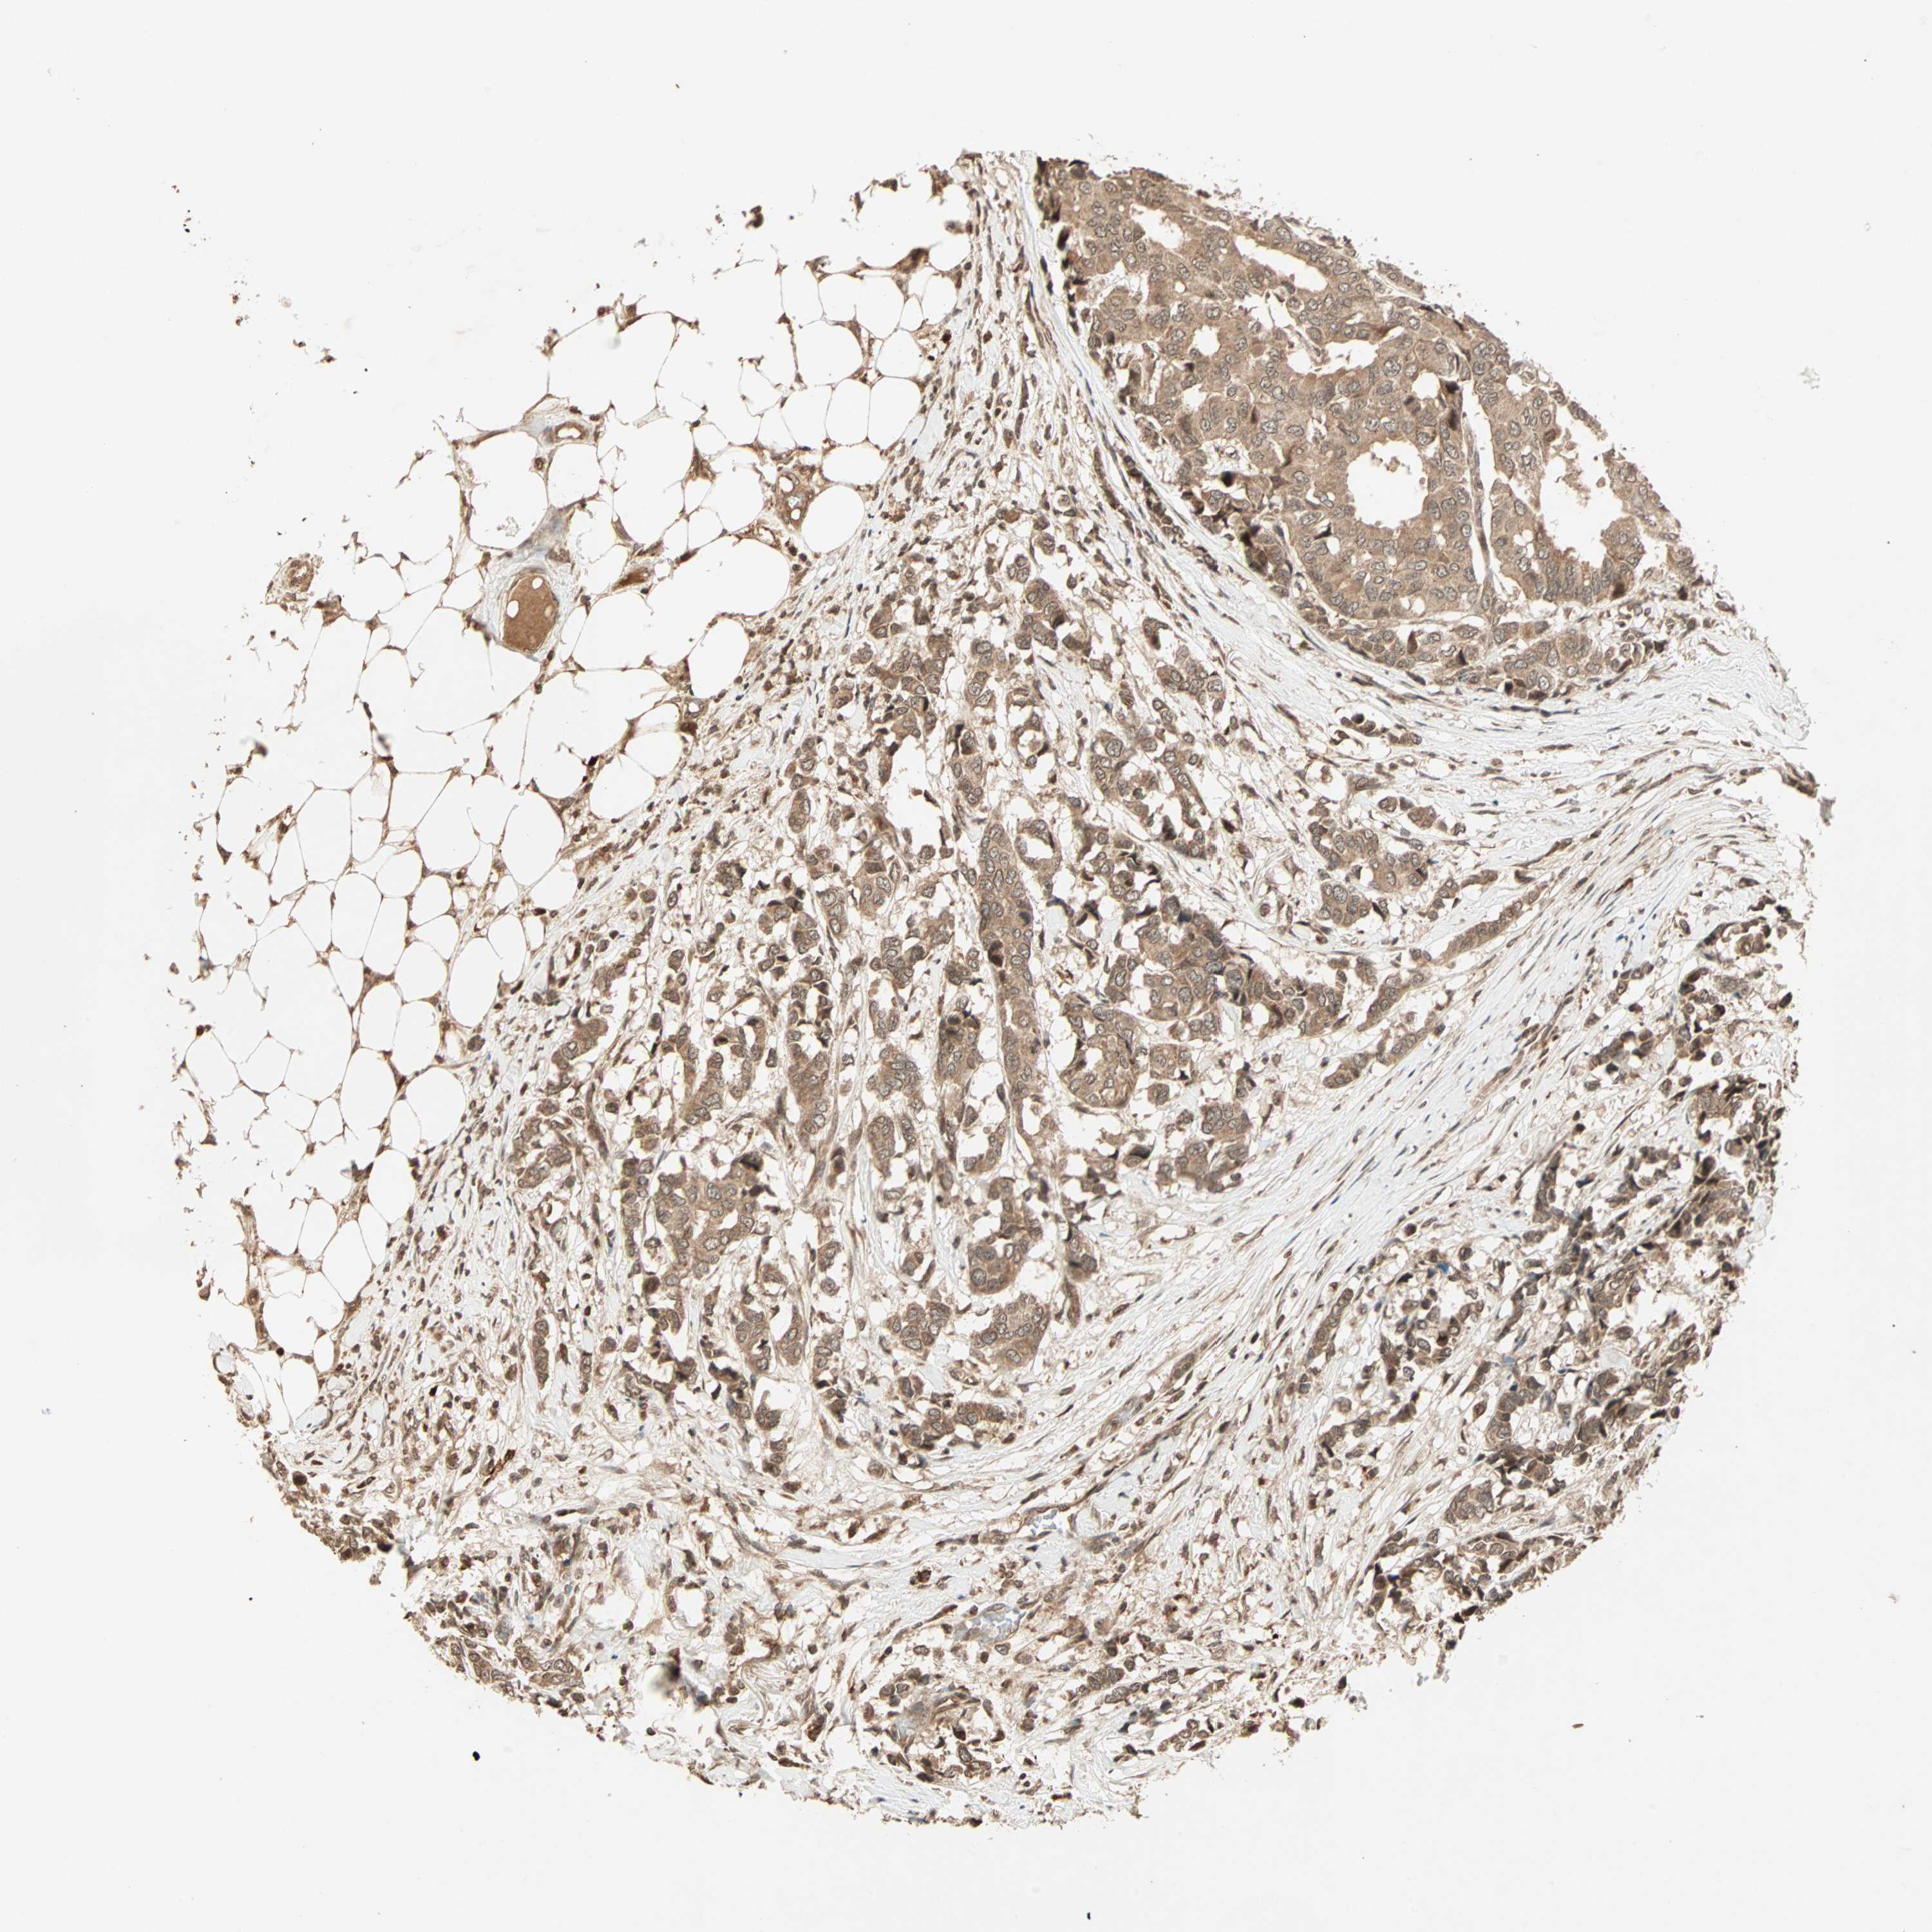

BRCA TCGA BRCA VALIDATION PROTEIN EXPRESSION

ANTIBODIES

AND

VALIDATION